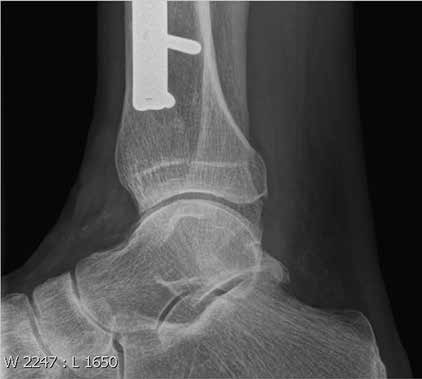

Als Beispiel dient ein 75-jähriger pensionierter aktiver Patient mit einer sekundären Sprunggelenksarthrose nach einer distalen Tibiaschaft-Fraktur vor rund 25 Jahren (Abb. 1). Als wichtige Nebenerkrankung ist eine fortgeschrittene pAVK bekannt, zudem besteht ein persistierender Nikotinabusus. Der Patient klagt über Schmerzen, die ihn vor allem bei längerem Gehen und im steilen oder unebenen Gelände stark stören. Da er gerne längere Wanderungen unternimmt, fühlt er sich in seiner Lebensqualität stark beeinträchtigt. Knorpelaufbaupräparate und Physiotherapie sind ohne Erfolg geblieben, die Schmerzmitteleinnahme möchte der Patient nicht weiter ausbauen. Für ein chirurgisches Vorgehen – Sprunggelenksarthrodese oder Sprunggelenksprothese – ist die Arthrose nicht genügend fortgeschritten.